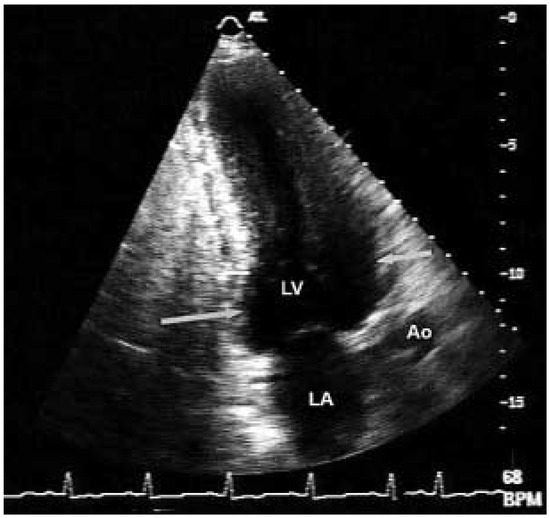

Apikale Hypertrophe Kardiomyopathie—Vom EKG zur Diagnose

by Susanne Buchholz and Thomas Herren

Cardiovasc. Med. 2005, 8(5), 204; https://doi.org/10.4414/cvm.2005.01099 - 27 May 2005

Viewed by 129

Abstract

Der 54jährige, aus Sri Lanka stammende Patient verspürte bei seiner Tätigkeit als Landwirt eine zunehmende Müdigkeit unter Belastung sowie ein «Schweregefühl» in der Brust [...] Full article

Show Figures

Figure 1